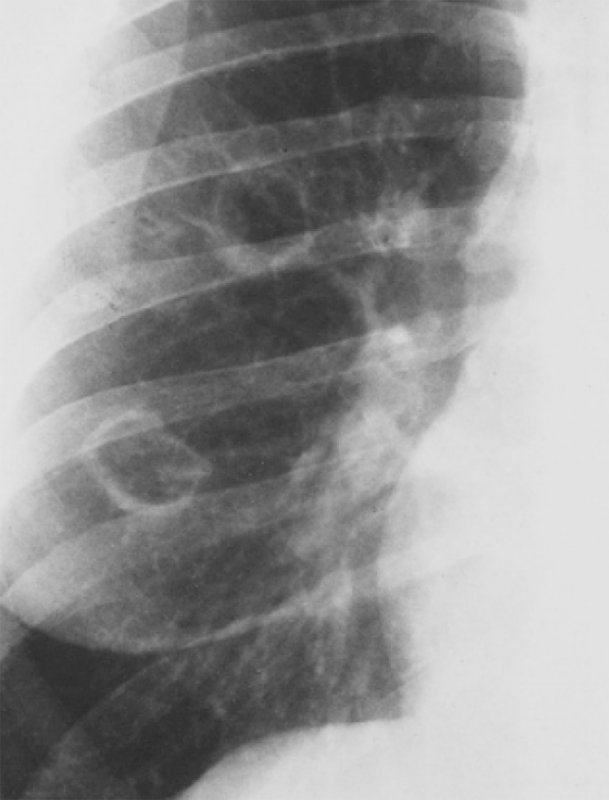

Синдром Гудпасчера – системный капиллярит, характеризующийся преимущественным поражением базальных мембран гломерулярного аппарата по типу гломерулонефрита (с гематурией) и альвеол легких по типу геморрагического пневмонита (с легочными кровотечениями). Рентгенологическая картина характеризуется появлением участков альвеолярной инфильтрации в легких. На рисунке 3 продемонстрированы интерстициальные изменения в легких, характерные для этой патологии.

Рисунок 3. Синдром Гудпасчера: Интерстициальные изменения в легких. Усиление интерстициального компонента легочного рисунка с обеих сторон, определяются ретикулярные и множественные мелкоочаговые тени. Изменения наиболее выражены в нижних и средних отделах легочных полей